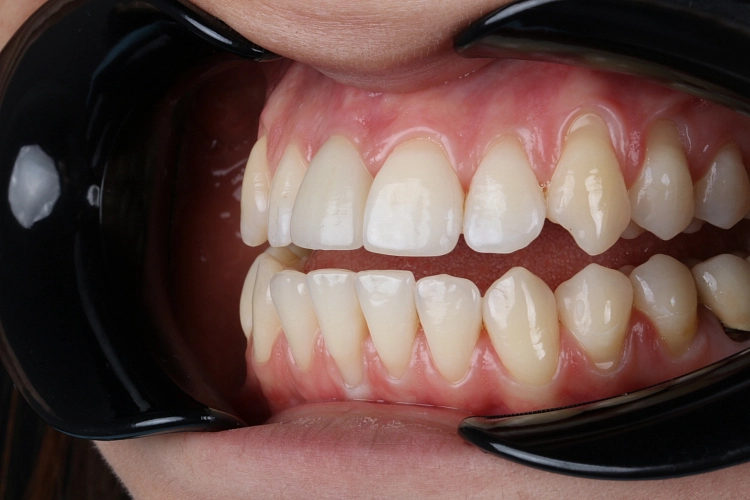

Виниры

От 33 500 Виниры фото